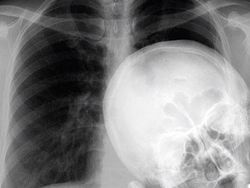

Seperti ini bayi kembar yang dempet. (Foto: Brightside)